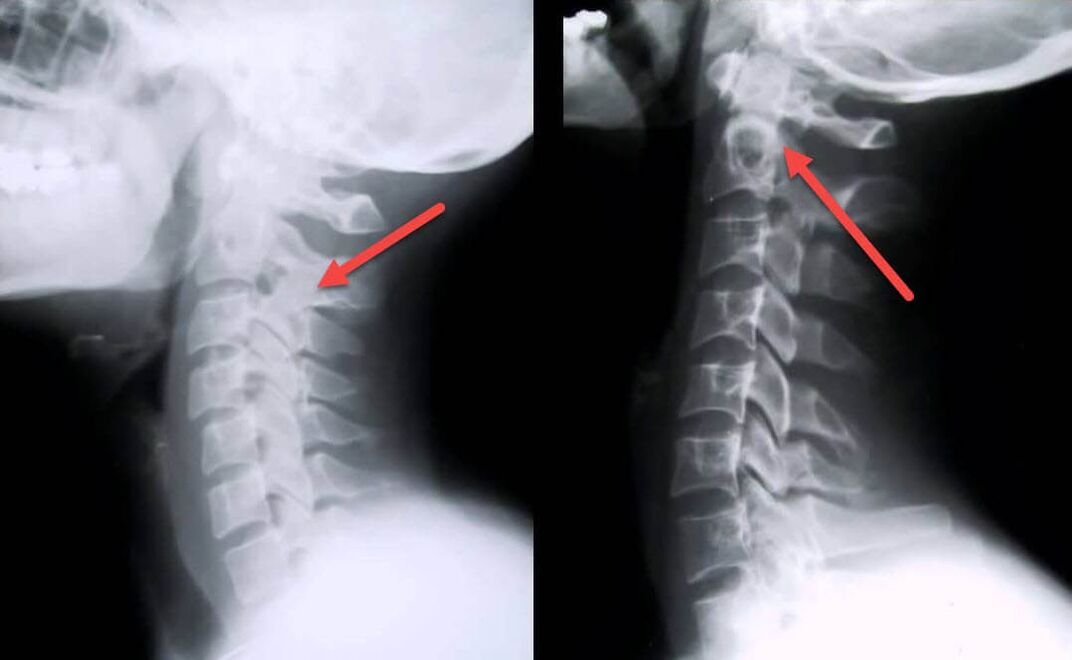

The most informative diagnostic procedure is x-ray.1st degree pathologies correspond to the 1st or 2nd radiological stage.The images obtained visualize the typical signs of the disease.

| Radiological stages of cervical osteochondrosis of the 1st degree | Characteristic signs |

|---|---|

| Step 1 | Minor changes in spinal curvature in the cervical region, affecting one or more segments |

| Step 2 | Slight thickening of the intervertebral discs, deformation of the uncinate processes, straightening of lordosis, minor growths of bony structures |